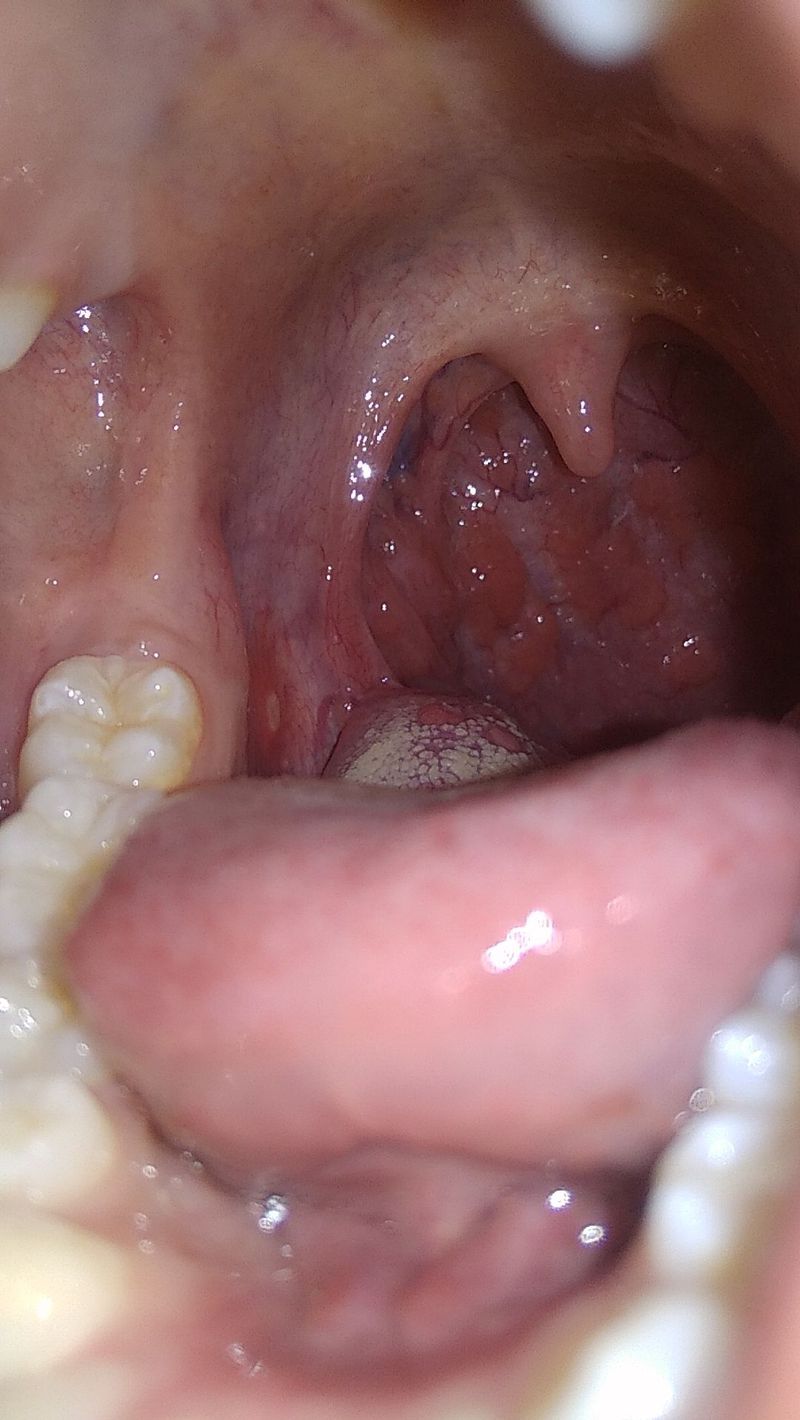

Canker sores..

Aphthous sore in inner lining of cheek.. Its more painful to eat, speak, swallow,. It takes weeks to heal... Should avoid spicy food etc.. To get relief apply ice to it and also rinse with salt water or baking soda..